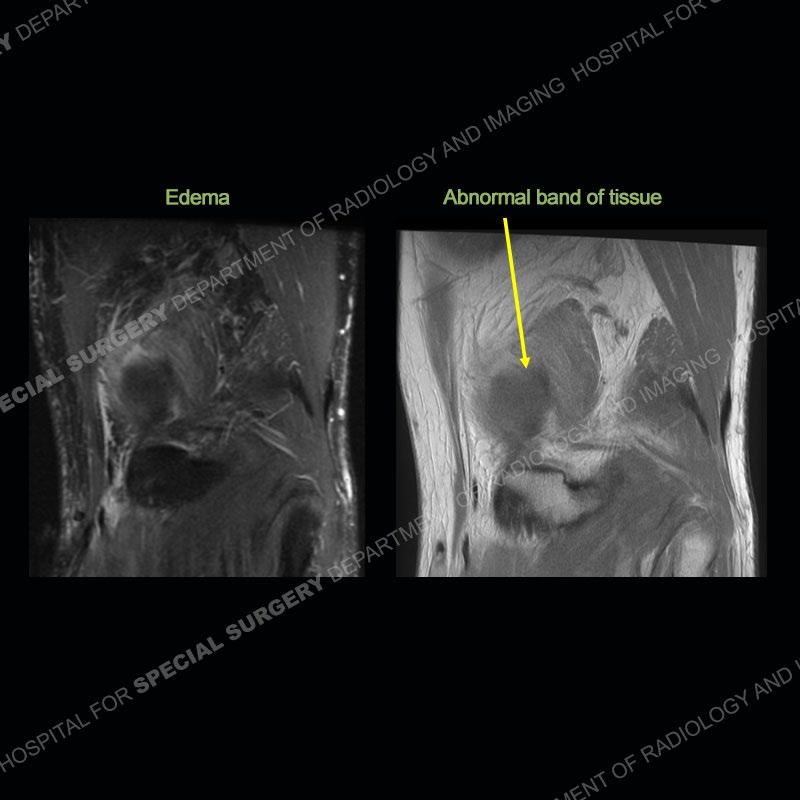

The radiographs show degenerative change of the medial compartment and a varus knee, but they are not germane to this case. No acute bony injury is present. The MRI shows edema of the posterior medial knee/soft tissue and a focal area of a partially disrupted low signal structure. The details are kept at a minimum in the findings of this case on purpose.

Diagnosis: Partial Disruption Medial Head Gastrocnemius (MHG)

The findings were kept purposefully vague as identifying the structures early on takes away a lot of the diagnosis. An uncommon entity and one of which we do not see a lot. Enthesopathic changes and tendinosis are seen as are distal MHG injuries, but proximal tears are rarely present. This case highlights a number of points. One, it almost always comes down to anatomy. Perhaps not a structure we normally spend too much time on, except save for diagnosing a Baker’s cyst, but knowing where this structure and all structures exist in all three planes is imperative. Second, when you think you are making a “call” or finding that you have never made before, step back and think is this just the abnormal presentation of a common pathology. That situation arises much more frequently. Third, if you look at it once, twice, and probably a third time and are confident in your odd or very rare diagnosis, stick to your guns. Especially, when it comes down to anatomic structures, the proof will be in the images.

Fourth, use all imaging planes and different pulse sequences to make your diagnosis. The edema highlighted in this case can be seen as the obscuration of fat on the PD images but is much easier to perceive as the high signal on the IR pulse sequences. The actual disruption of the MHG myotendinous junction is only able to be seen on the axial images. On the sagittal and coronal images, we get a sense something is wrong but hard to be exact. Lastly, when you look at a study and something just seems off (as I would say the sagittal and coronal images do with that dark band of tissue posteriorly), listen to yourself and go through the study slowly and meticulously. Most of the time you will find you were right, and something indeed is present.